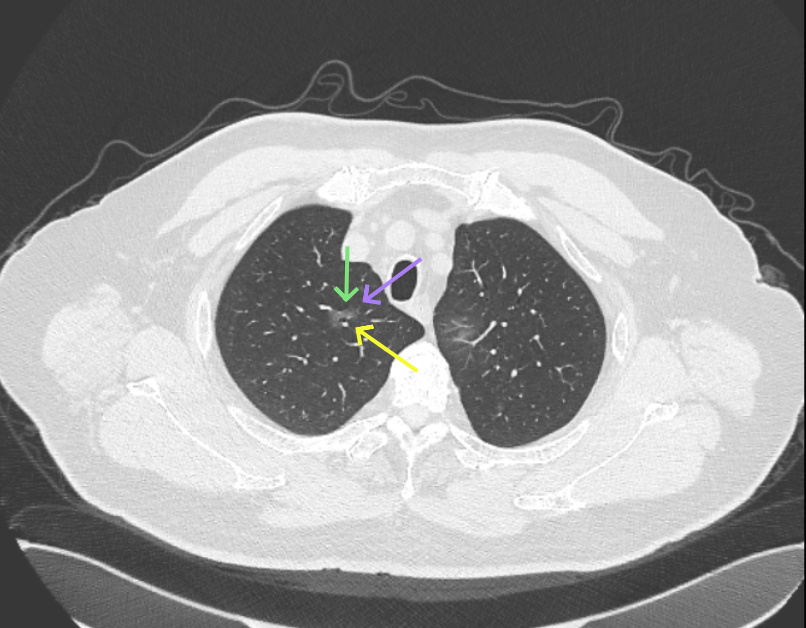

方形的是25年的,红色的主病灶,磨玻璃密度伴少许略偏高点密度,但还说不上典型混合磨玻璃病灶,考虑原位癌或微浸润性腺癌可能性大;蓝色的轮廓与边界欠清,位置靠上叶中央,无法段切或楔切;黄色的多发均淡而纯,分布在两肺。圆形粉色的是主要的两处23年时的样子,对比说不上很明显进展。鉴于若手术得切肺叶,何况两肺他处仍的结节,年纪又74了。我倾向保守点,先6-9个月复查,等进展并风险增加再来考虑怎么办的事。意见供参考!

病灶没有确切纵隔窗可见的实性成分,但与血管关系较为密切。